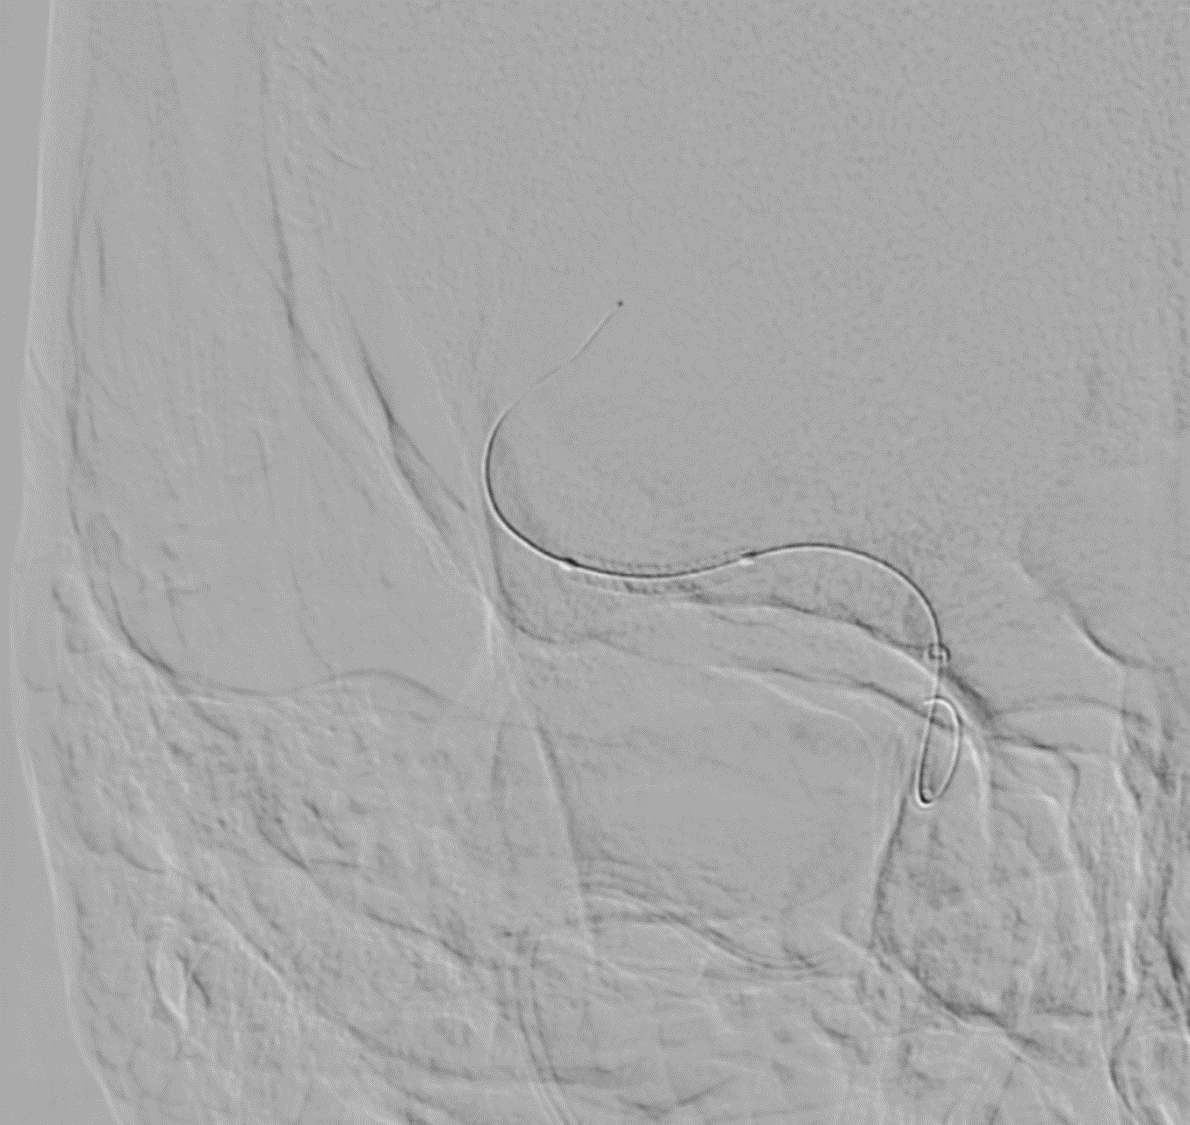

MRV shows left Transverse and sigmoid sinus thrombosis. No improvement after 2 days of IV heparin. Pt requires heavy sedation, ventilation for headache/agitation.

DSA also confirmed the extensive clot. In view of her recent LSCS 20 days ago, we were hesitant about giving IV lytics (urokinase infusion). Hence went in with an ACE 5 Max catheter and sucked out a mountain of clot